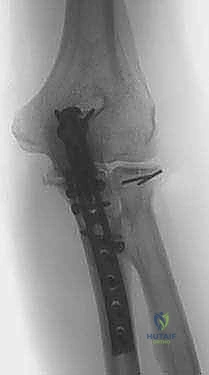

TECH FIG 2 • A,B. Preoperative and postoperative radiographs demonstrating open reduction and internal fixation of the radial head component of the Monteggia fracture.

* Pearl: After fixation, gently range the elbow and forearm through a full arc of motion to confirm stable fixation and absence of impingement. Use fluoroscopy to confirm concentric reduction of the radial head within the capitellum.

TECH FIG 2 • ( continued ) C. Postoperative radiograph of a Monteggia fracture in which the radial head fracture needed to be replaced.

* Definitive Fixation: Apply a rigid plate to the dorsal cortex of the ulna, extending proximally over the olecranon. This plate will typically be a pre-contoured olecranon plate or a specifically designed Monteggia plate.

TECH FIG 3 • ( continued ) D. Final fixation for most Monteggia fractures is with a rigid plate applied to the dorsal cortex.